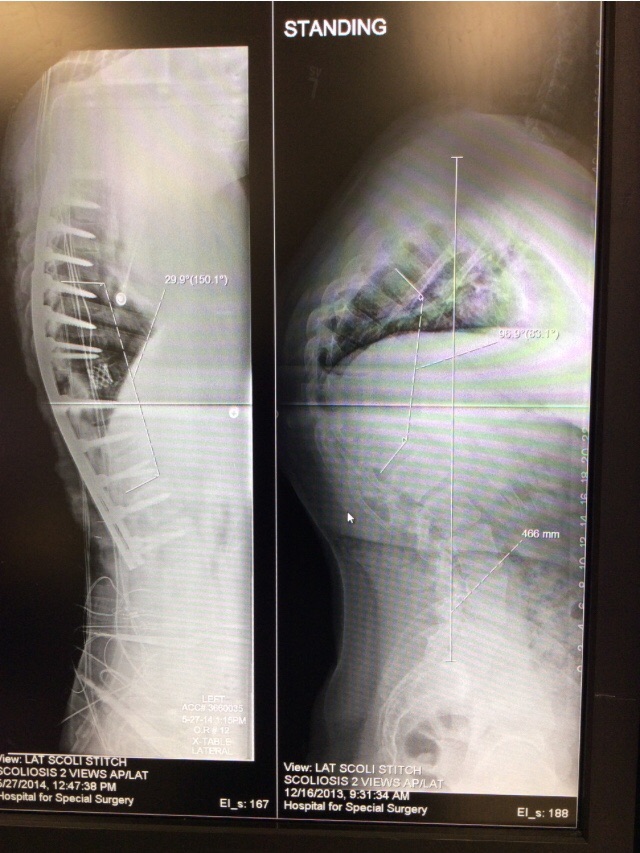

Before coming to HSS, I saw numerous doctors concerning my Scheuermann's Disease. Many of them could only take x-rays and tell me that they can't help me and do not know anyone who could help. With a 98 degree curvature and having doctors say they can't help, I felt hopeless. But then I found HSS and made an appointment with Dr. Boachie in December of 2013. There he was able to inform me more about my condition and set up an appointment for my surgery in May of 2014. Leading up to the surgery I was definitely scared, but my confidence in Dr. Boachie and Dr. Kim was overwhelming. Long story short, my surgery was a major success and my quality of life was dramatically increased. The constant pain I had associated with my condition was relieved, my breathing improved and my overall height went from 5'11" to 6'4". The picture I put up is me attending the Football Hall of Fame Ceremony less than 3 months post surgery. I was able to walk around all day without taking a break, whereas when I had my curvature I would need to take numerous breaks due to the pain. Dr. Boachie and Dr. Kim changed my life in so many different ways, they gave me my life new direction and I can't thank them enough for what they did for me. Them along with HSS gave me hope when no one else could.